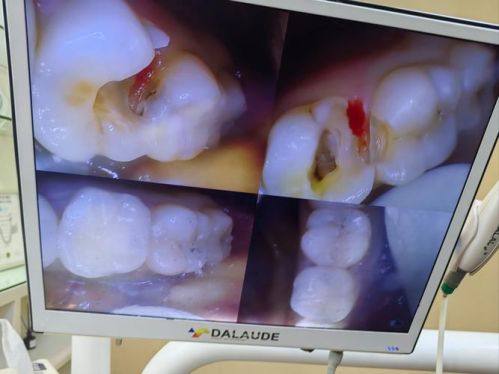

牙齿治疗:牙齿治疗涵盖了多种口腔疾病的诊疗。对于龋齿,毛医生会及时去除龋坏组织,然后进行填充修复,防止龋齿进一步发展。对于牙髓炎、根尖周炎等疾病,他能熟练进行根管治疗,消除炎症,保留患牙。在牙周病治疗方面,他会根据患者的病情制定个性化的治疗方案,包括洁治、刮治等,有效控制牙周炎症,维护口腔健康。

精良的技术设备:毛治军 医生所在的诊所和门诊部配备了精良的口腔医疗设备。这些设备能够为诊断和治疗提供更正确的依据,提高治疗的精度和成效。例如,在种植牙手术中,精良的设备可以帮助医生更精细地定位种植体的位置,提高种植的成功几率。同时,精良的设备也能减少患者在治疗过程中的不适感。